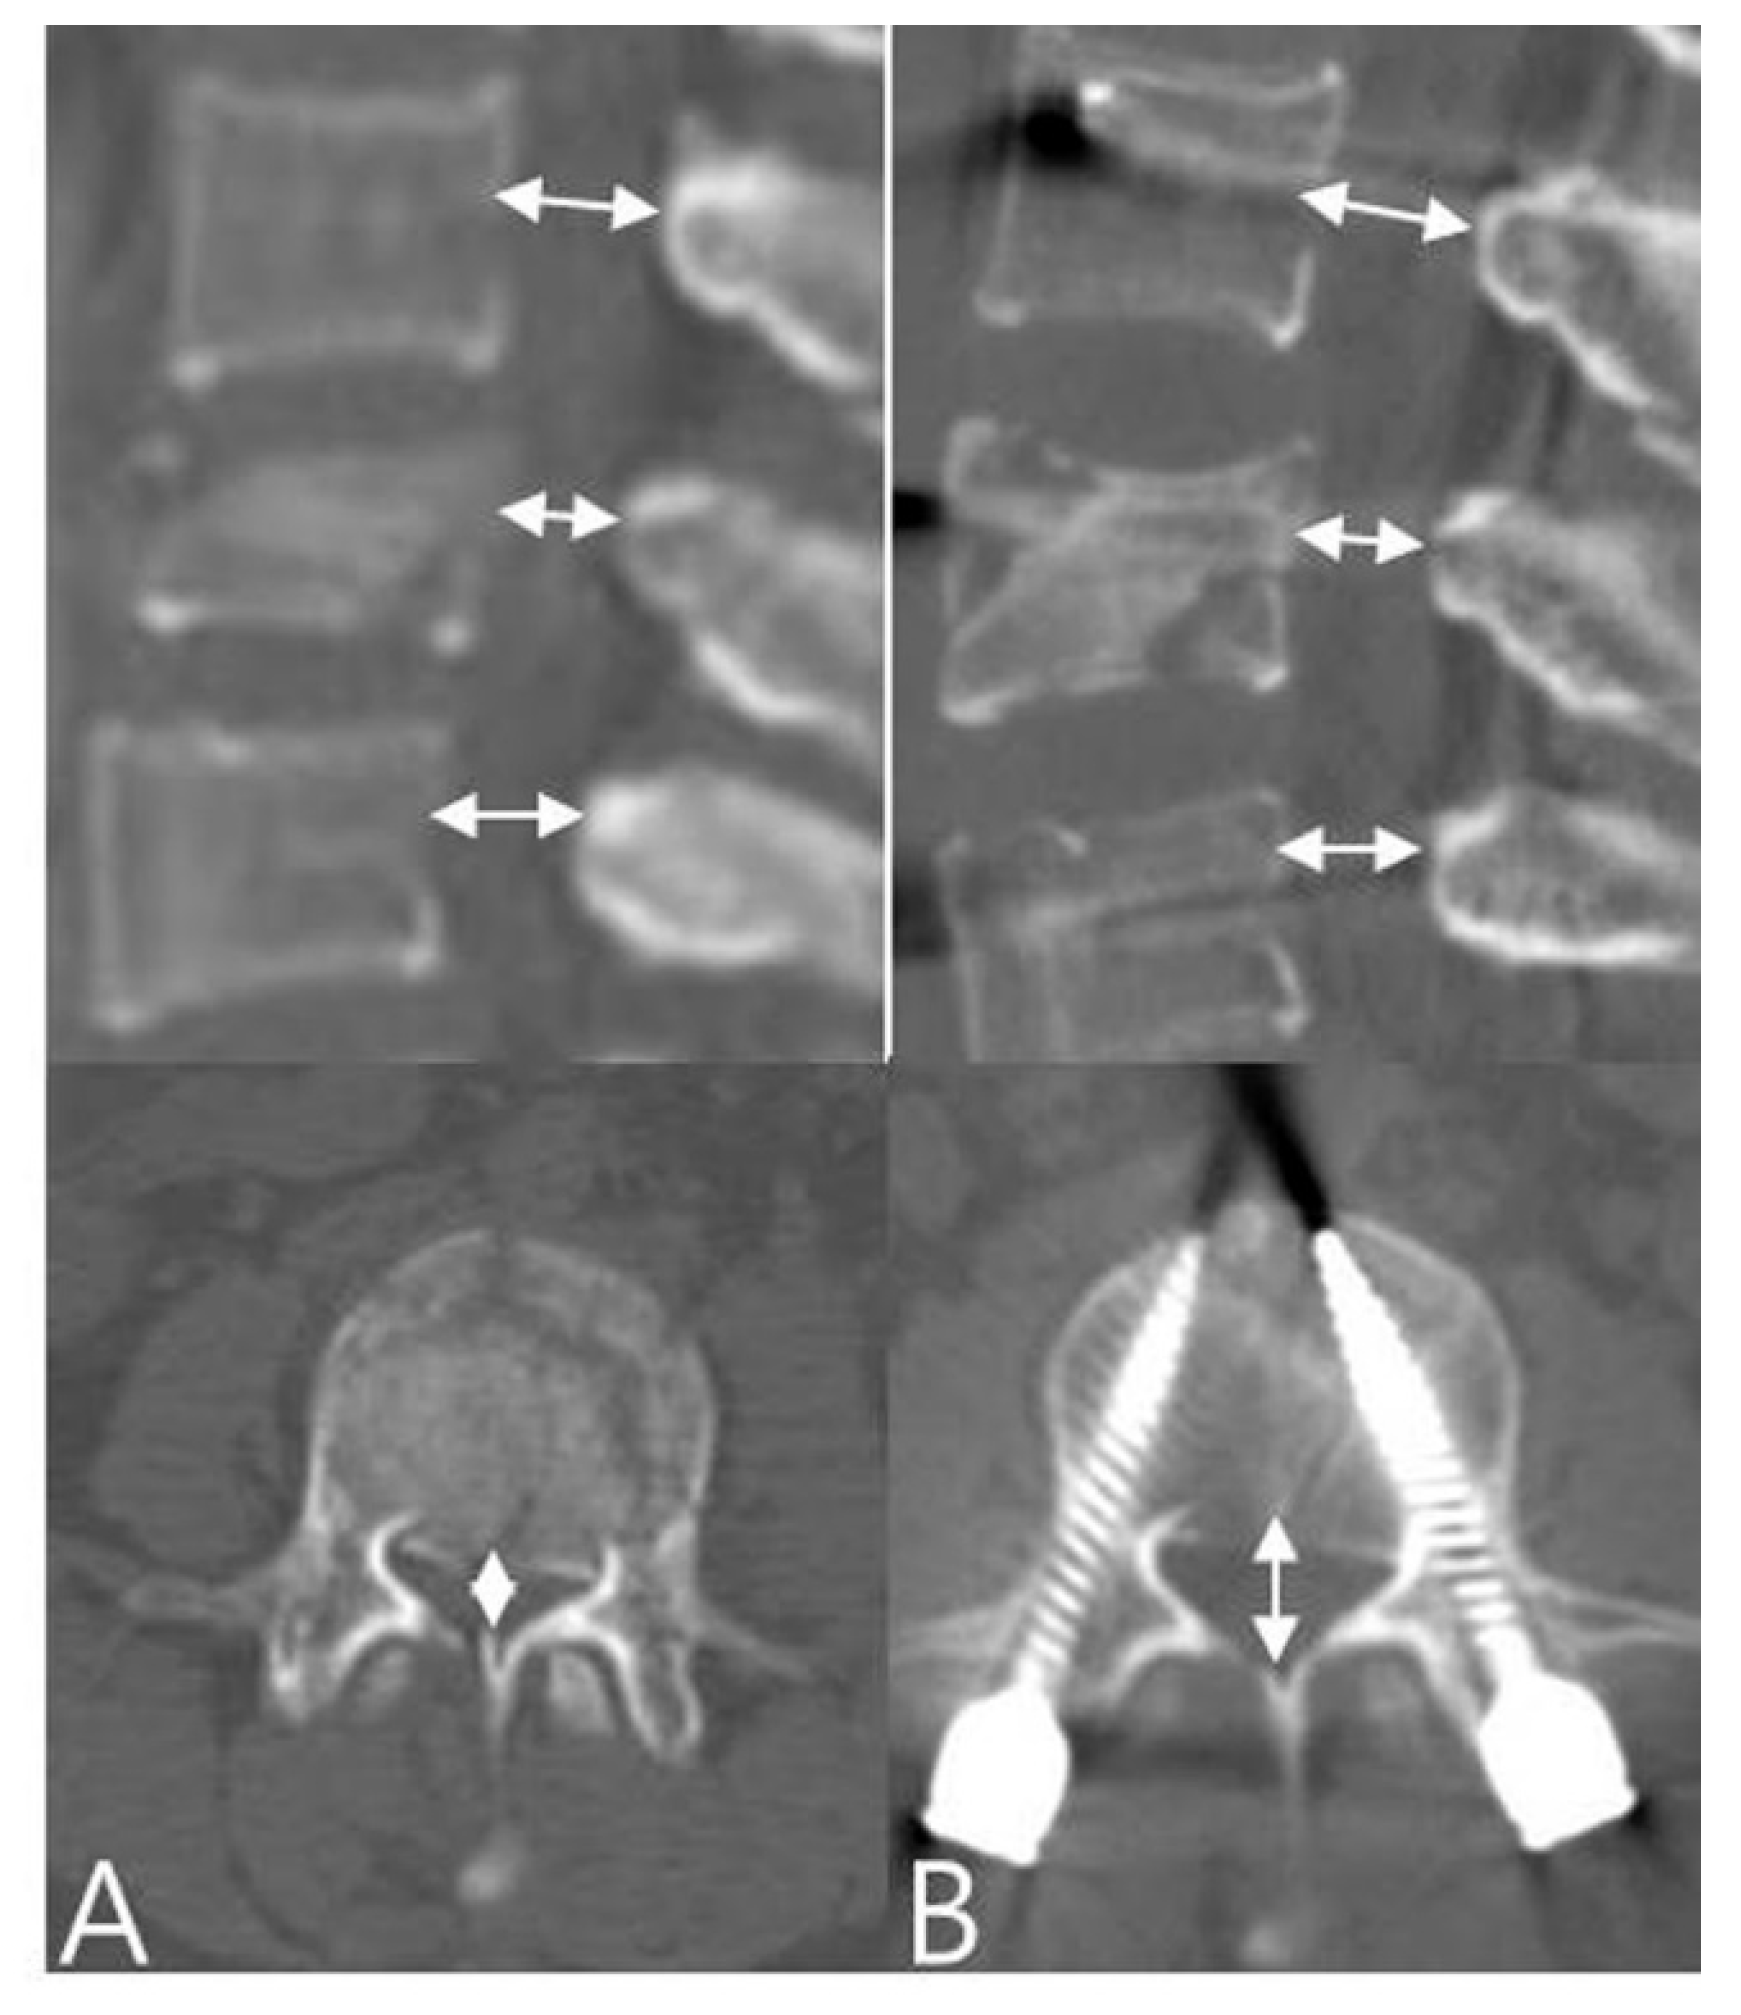

2.3. Radiologic Evaluation and Clinical Assessments

3.1. Radiographic Outcomes

| Spinal canal encroachment (%) | |||

| Preoperation | 38.6 ± 11.4 | 36.4 ± 17.6 | 0.412 |

| Postoperation | 14.8 ± 9.7 | 22.3 ± 10.3 | <0.05 |

| Final follow-up | 15.1 ± 10.8 | 23.7 ± 11.6 | <0.05 |

| p value (pre-final) | <0.05 | <0.05 |